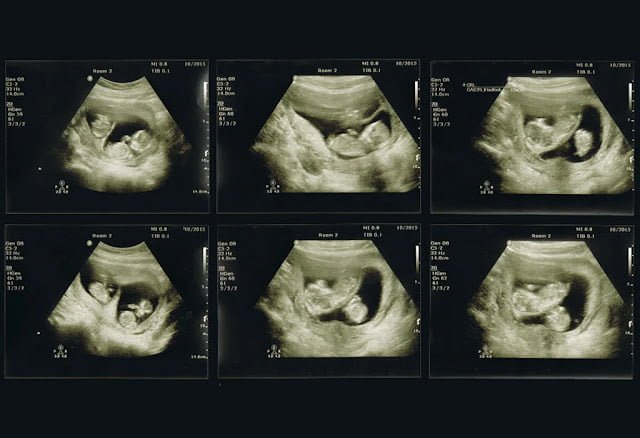

Kaybolan ikiz sendromunun teşhisi çoğunlukla ultrason yardımıyla yapılır. Eğer erken bir ultrason, ikiz gebeliği gösteriyorsa fakat ebeveynde düşük semptomları ya da beklenenden düşük hCG seviyeleri gözlemleniyorsa veya Doppler ile sadece bir bebekten kalp atışı tespit ediliyorsa, bu durum kaybolan ikiz sendromuna işaret edebilir.

Bir takip ultrasonu, ikizlerden birinin kaybını doğrulayabilir. Bu ultrason, sağlıklı gelişen bir bebeği, geri çekilen diğer ikizle birlikte gösterebilir. Doğumdan sonraki plasenta incelemesi de bu durum hakkında önemli bilgiler sunabilir. Eğer ikiz kaybından önce herhangi bir ultrason yapılmamışsa, kaybedilen ikizin varlığı kesin olarak belirlenemeyebilir.